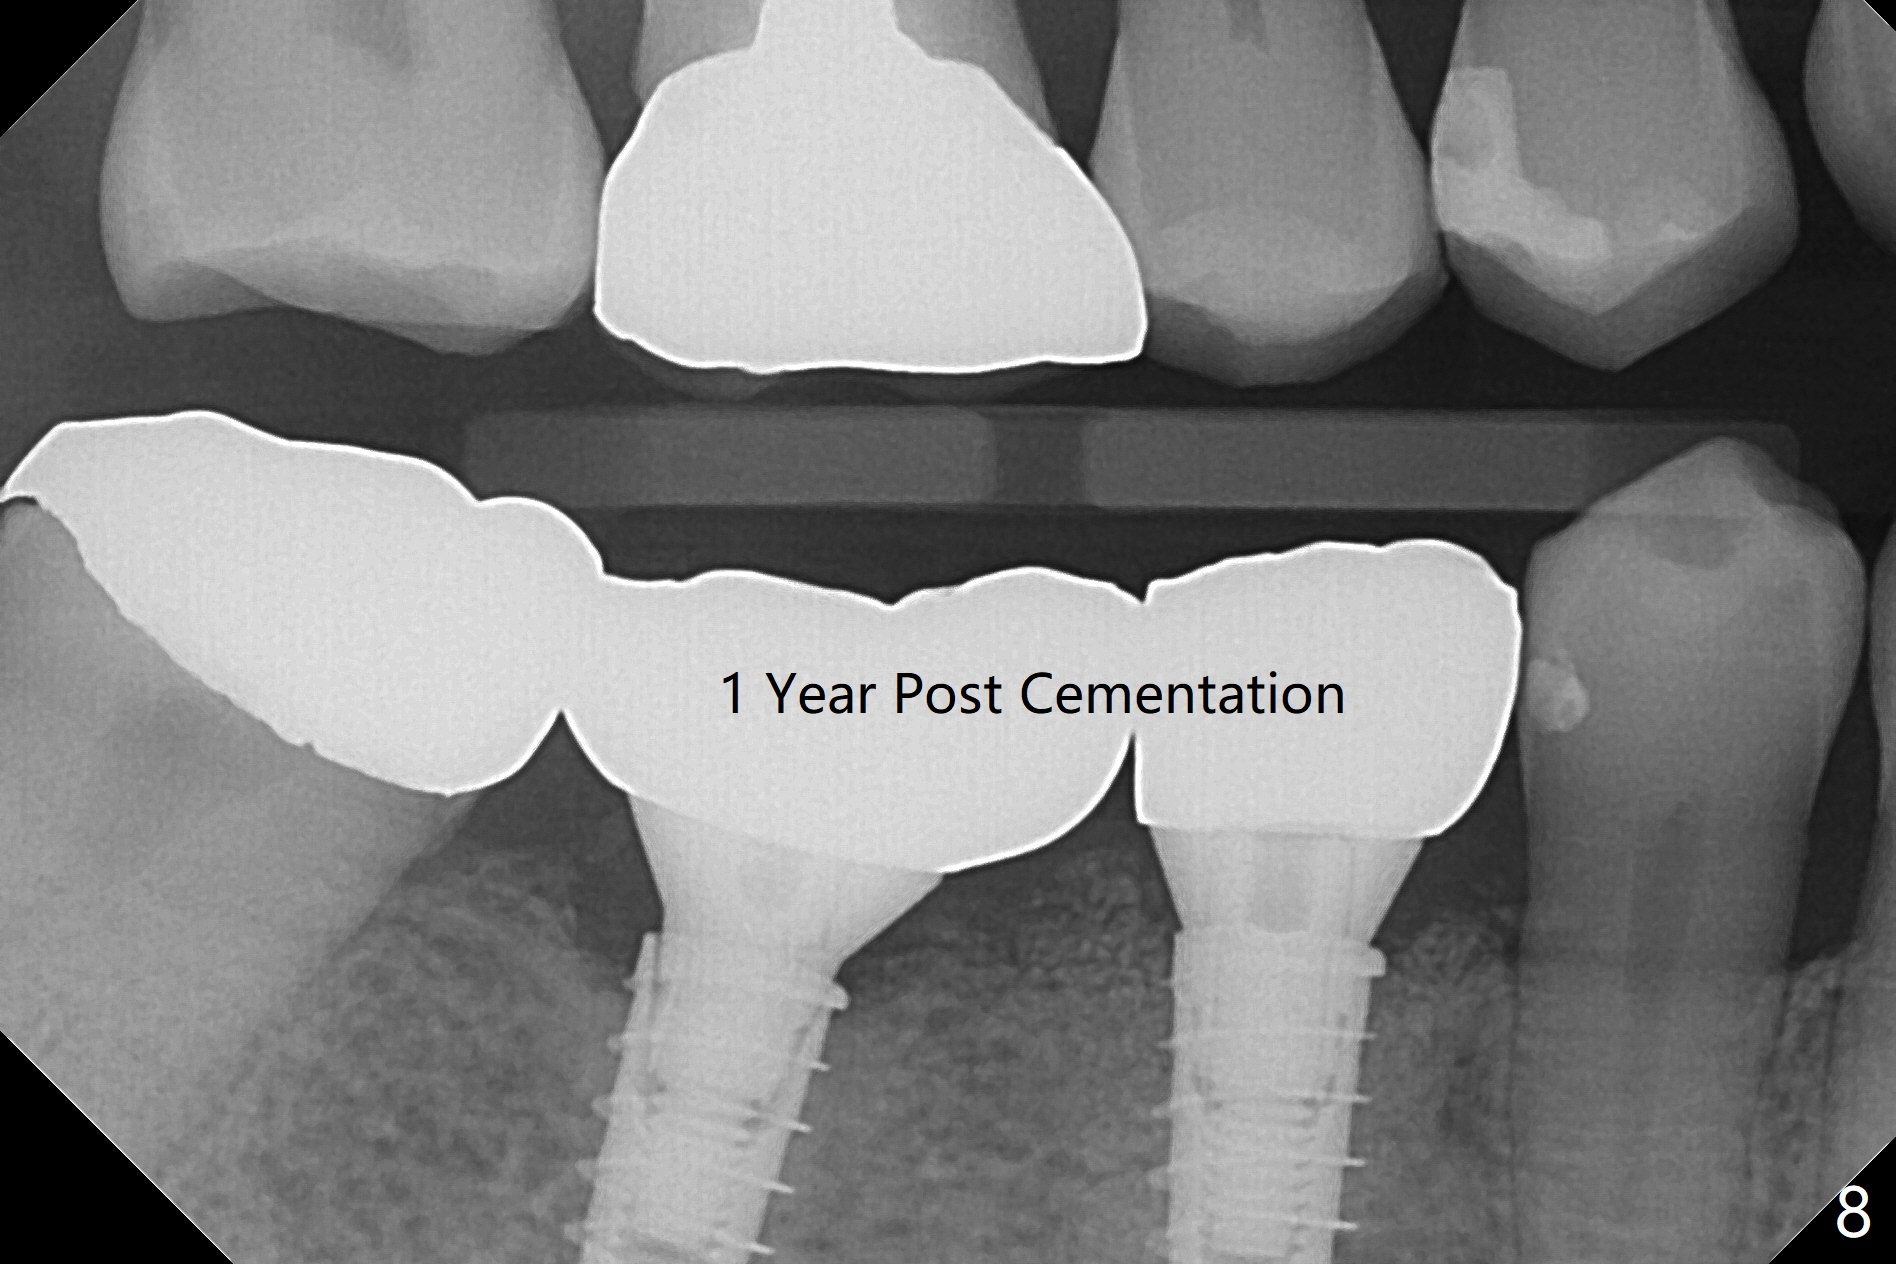

After incision, the ridge at #29 and 30 is found ~ 5 mm wide buccolingually. To place a 4x11 mm IBS implant at #30, the ridge is expanded using BEB technique (bone expansion and bending, Fig.1). It appears that the initial osteotomy at #29 is mesial (Fig.1 yellow dashed line: the distal surface of the root of the tooth #28). After moving the osteotomy distal, the final implant position at #29 (4x11 mm) is within normal limit (Fig.2). The bone at #29 seems to be not so dense that bending (using 1.6 mm drill) is not necessary (using Magic Split and Magic Expanders 3 and 3.8 mm). Later the implant at #30 (4x11 mm) is placed deeper (Fig.3). After placing bone graft around the implants/abutments and suturing, the ridge looks wider with apparent formation of the gingival bands around the abutments (Fig.4 *). Three months and a half postop, bone loss is minimal (Fig.5) and gingival bands forms around the abutments (Fig.6). Fig.7 is taken 1 month post cementation (panoramic X-ray). The patient chews normally 1 year (Fig.8) and nearly 2 years (Fig.9,10) post cementation. The crown at #31 needs recementation 2 years 7 months post #30 cementation; the incomplete seating of the abutment was noted for the first time (Fig.11). Five months later the patient is going to be retired and wants to travel abroad. After approval, the access hole was reopened; articulating paper shows under occlusion of the crown (Fig.12). Since the gap between the abutment and the implant is large, the abutment/crown complex seems to be necessary to be turned (Fig.13 curved arrow). The proximal surfaces of the crown need to be trimmed (straight lines). After turning, the crown sits down with screw tightening; the patient feels pain from the gingival cuff (Fig.14). After turning, the abutment appears to be completely seated (Fig.15). In fact the mesial and distal surfaces of the crown should have clearance from the neighboring teeth (Fig.14) so that pick-up impression is able to hold the crown/abutment complex securely (Fig.16: *). The crown is separated from the abutment after crown repair. They are seated together (loose connection) using the crown as a guide to seat the abutment. BW is taken without the crown. It appears that the abutment remains seated completely (Fig.17). The apical space is equal between #29 and 30 (Fig.17, as compared to Fig.5).